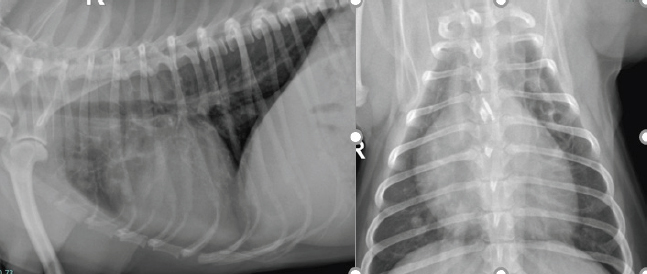

At the 2-week revisit, the owner reported the coughing had resolved. Radiographs of the chest were repeated and revealed marked improvement with the larger lung opacity on the left cranial lung field becoming significantly smaller. The dose of prednisolone was reduced to 1 mg/kg PO q 24 hours for 2 more weeks. Continued clinical improvement was reported by the owner and was documented in the thoracic radiographs at the 4-week revisit. Complete resolution of clinical signs and radiographical lesions was observed at week 10 (Fig. 6). The dose of prednisolone was tapered off over the following 8 weeks and then stopped. The dog is currently doing well with no signs of recurrence over 1 year after the initial presentation.

Fig. 6. Left lateral and dorsoventral thoracic radiographs 10 weeks following corticosteroid treatment.